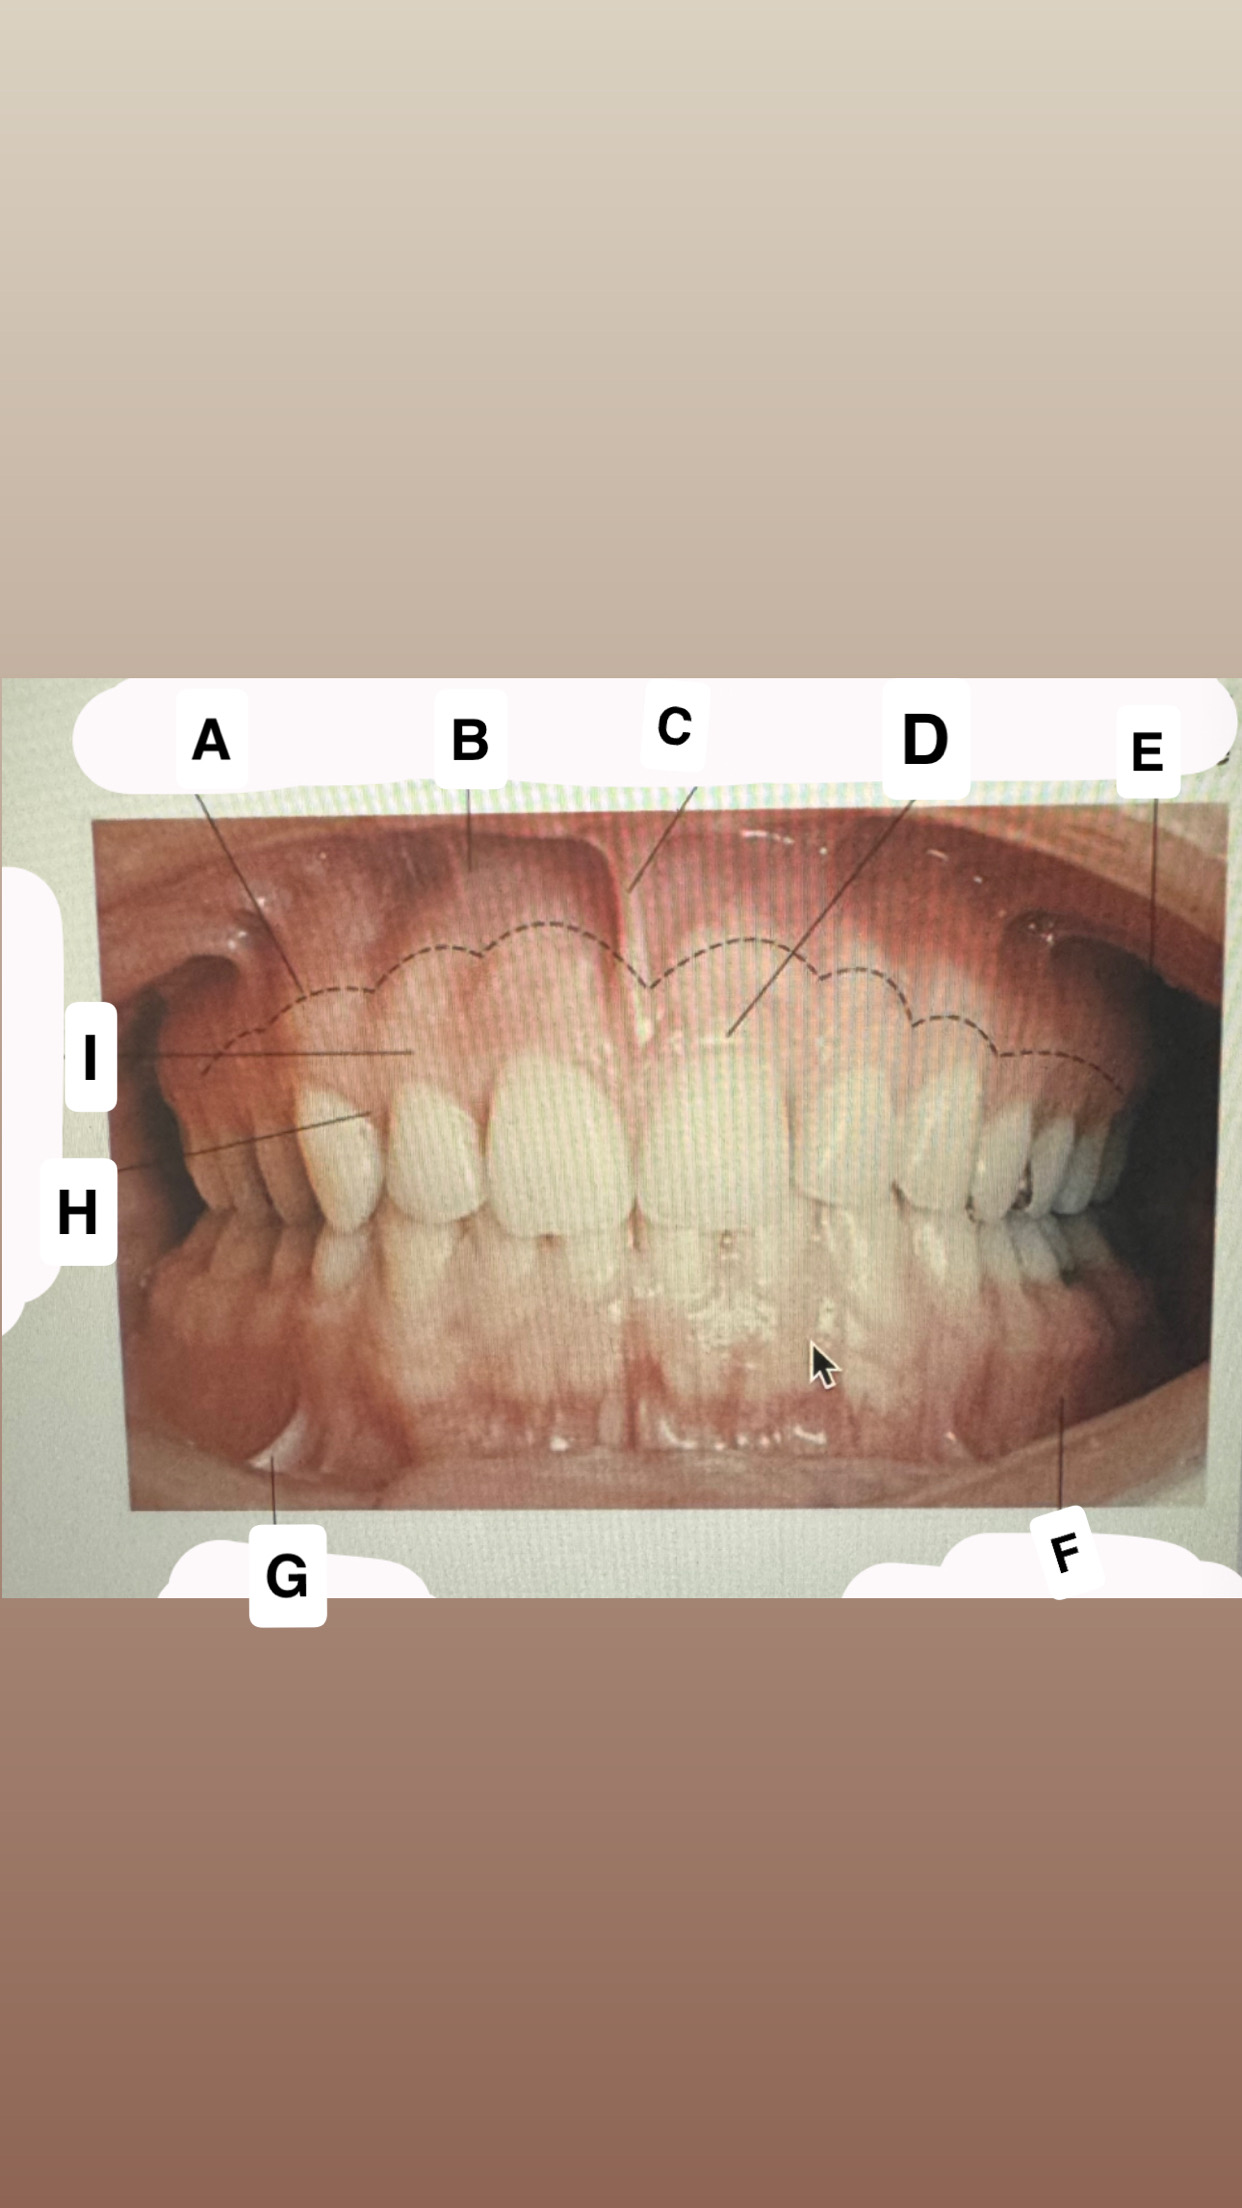

<p>Identify A</p>

- Incisive papilla

<p>Identify C</p>

• Palatal glands

<p>Identify D</p>

Soft palate

<p>Identify H</p>

Palatal rugae

<p>Identify I</p>

Lingual (palatal)

gingiva

<p>Identify J</p>

Uvula

<p>Identify K</p>

Palatine tonsil